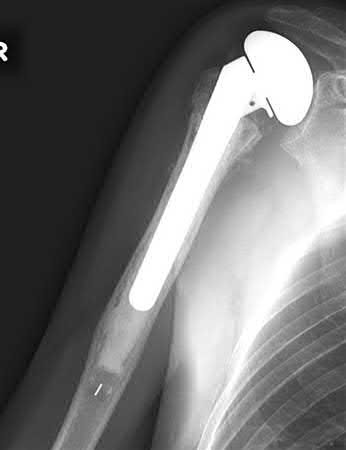

A 44-year-old male is struck by a vehicle while riding his bike. In the trauma bay, he complains of right shoulder pain . Upper extremity physical exam reveals no neurologic deficits, and an initial radiograph of the shoulder is shown in Figure A. A CT scan of the shoulder shows 1cm of posterior displacement of the tuberosity fragment. Which of the following is true regarding this injury?

The radiograph in Figure A demonstrates a posteriorly displaced greater tuberosity fracture. These injuries are often associated with anterior shoulder dislocations, and concomitant rotator cuff tears. The subscapularis attaches to the lesser tuberosity, and is not a deforming force. Open reduction and internal fixation (ORIF) is usually the treatment of choice, and it is well accepted that more than 5mm of displacement is an indication for surgery in patients that require overhead function of the arm.

Flatow et al evaluated 12 patients who were an average of five years status post ORIF of displaced greater tuberosity fractures. All fractures healed without postoperative displacement. Six patients had an excellent result and six had a good result.

Platzer et al retrospectively analyzed functional and radiographic results of 52 patients with operative treatment of displaced greater tuberosity fractures at an average time of 5.5 years from surgery compared to 9 patients with equivalent injuries treated non-operatively. Evaluation of the results of the surgical study group and the nonoperative control group, patients with reduction and fixat ion of greater tuberosity fractures had significantly better

results on shoulder function than did those with conservative treatment.